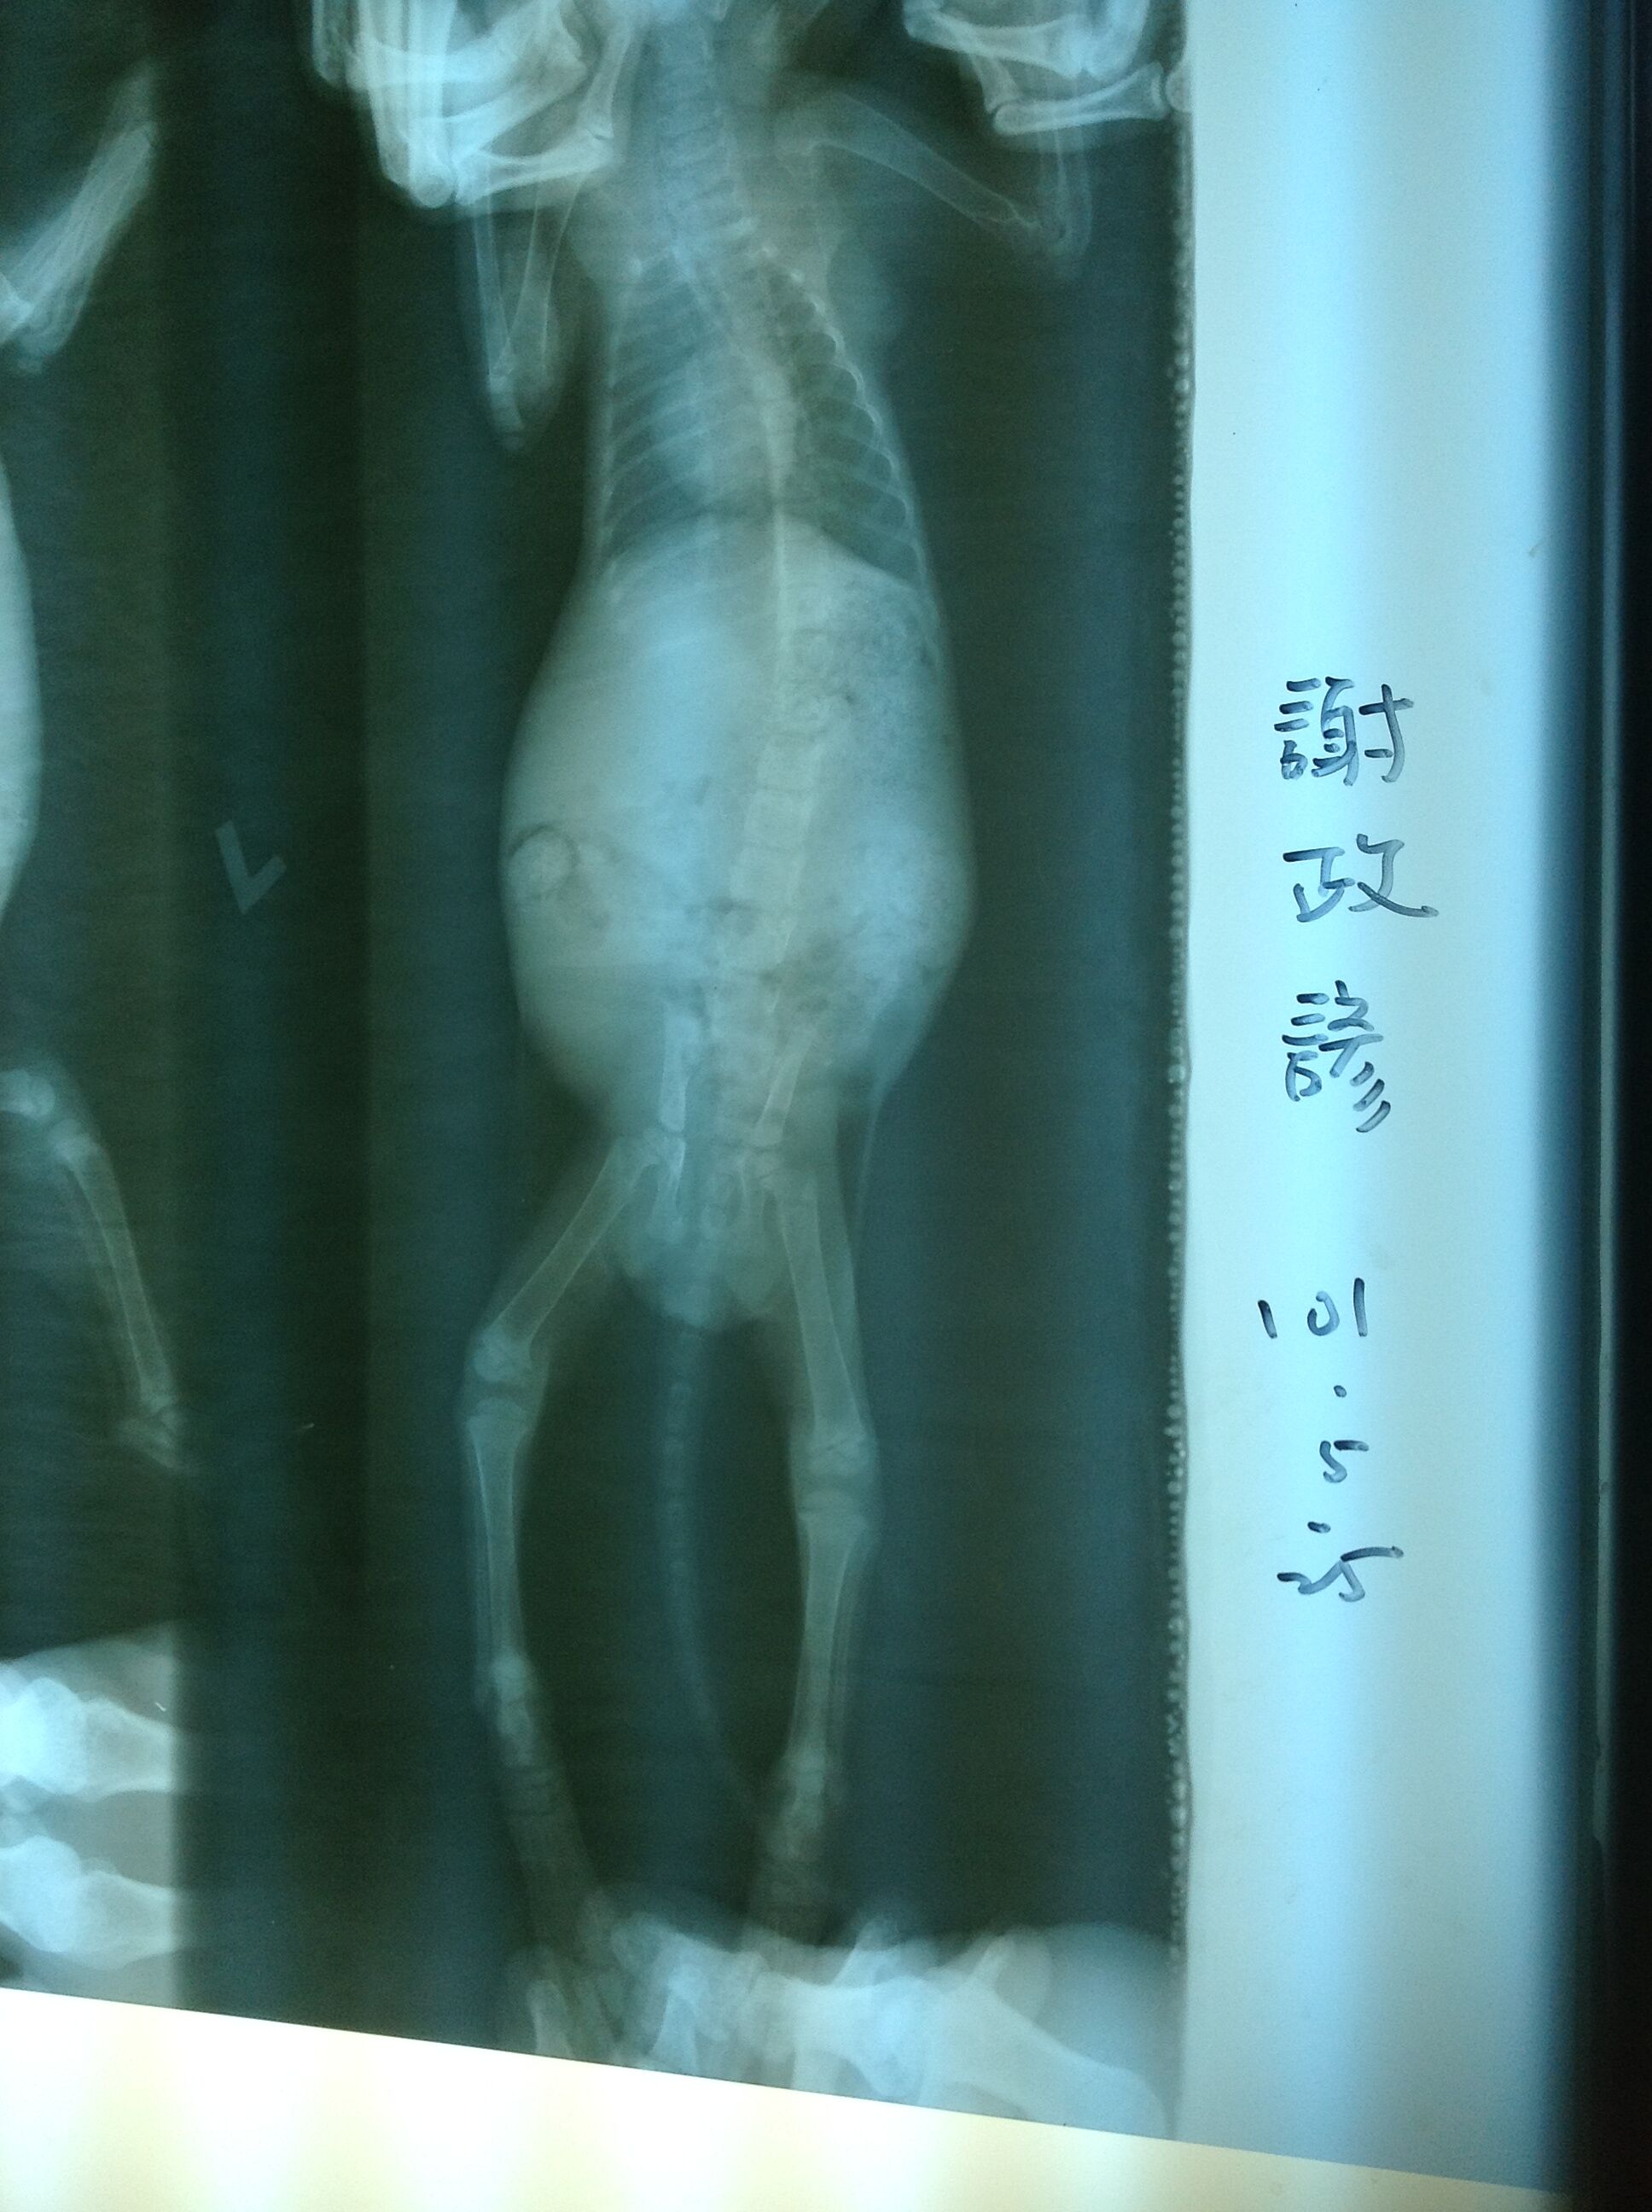

主題: 雲林癱瘓小玳瑁 申請者姓名: Vivi Sung 花色: 申請日期: 2012-07-09 13:27:50 申請者部落格: 申請者臉書網址: 所在縣市/合作醫院: 高雄市/回生動物醫院 治療費用: 10000元 需求人數: 23人 已結案 (2012-12-08 18:43:15) 報名人員: Yiling Tsai(已付款)、Carrie Hsu(已付款)、米粒(已付款)、五大仙(已付款)、小可(已付款)、潘逸群(已付款)、泡泡(已付款)、Sally Chang(已付款)、Kristy Lee(已付款)、Percy Wu(已付款)、曾慧娟(已付款)、迷迷(已付款)、路安(已付款)、吳東晏(已付款)、金鑫鑫(已付款)、H.l. Lai(已付款)、Vincent Hung(已付款)、劉蕊瑄(已付款)、裘裘(已付款)、Bei Bei Wang(已付款)、Forest(已付款)、Redd、Jillfly(已付款)、舒芙樂(已付款)、 候補人員: 小舟、小舟、 動物病情說明: 5/25於粉絲團求援遭車禍撞擊的小玳瑁.癱瘓且無法自行大小便..連絡後,南下轉診.雖然還未站起來,但針灸治療後,讓小貓已經可以自行上廁所,前腳相當有力,是個活潑的小傻妹..好心的醫生,因為不忍心貓咪將長期被關在醫院內,經過一番努力,已經為癱瘓小玳瑁找到後續家庭..感謝醫師體諒,因為半手愛心,也讓醫院造成的困擾.深感抱歉

1.5/25噴除蚤藥100

2.5/25 -7/6 住院41*100=4100

3.5/25.6/1.6/8.6/16.6/23打針拿一星期藥

600*5=3000

4.6/19五合一疫苗注射500(增強抵抗力減少病毒感染的機會)

5.5/26-7/1每隔三天針灸及溫灸一共12次300*12=3600

6.5/25.5/30.6/5驅蟲三次100*3=300(未計)

7.小貓洗澡200*2=400(未計)

醫療費用打9折11200*0.9=10080